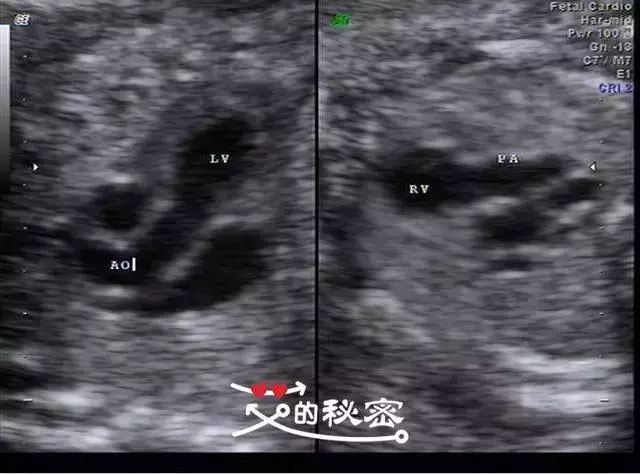

四维彩超现实三血管切面主动脉和肺动脉血流方